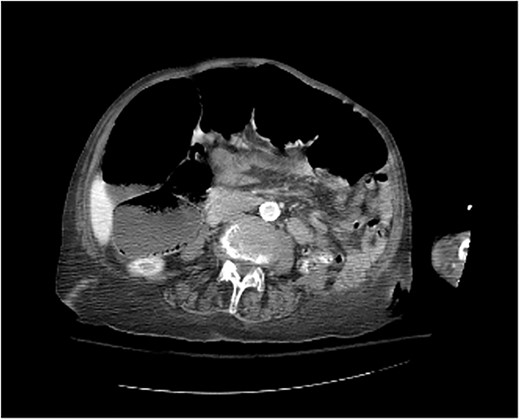

Physical examination was significant for right upper quadrant and epigastric tenderness with a mildly distended abdomen. On admission, the patient had a leukocytosis of 16.2. Imaging included computed tomography (CT) of the abdomen and pelvis showing the obstruction of the colon suspected because of a loop of colon herniated into the lower anterior chest, between the lower aspect of the sternum and the left heart border with mild mass-effect on the heart (Figs 2 and 3).

Morgagni hernia seen on CT abdomen and pelvis with contrast (sagittal view).